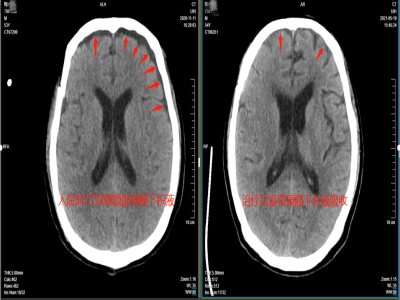

热爱美食乐天派,意外坠落受重伤去年9月份,虞先生在工地施工时,不慎从高处坠落,重型颅脑损伤+浑身多处骨折。

好在抢救及时,经过多次手术和及时的康复治疗,虞先生病情逐渐稳定,身体机能也在不断恢复,但是没法正常进食成了他的烦恼。

在吞咽过程中,当咽缩肌收缩波传导到环咽肌时,环咽肌的紧张度明显下降直至为零,食管上口即张开,食物(包括固体和液体食物)顺利进入食管。环咽肌的张力是由交感神经支配的,因为颅脑损伤虞先生的“神经司令部”受损,直接导致了他的吞咽困难。